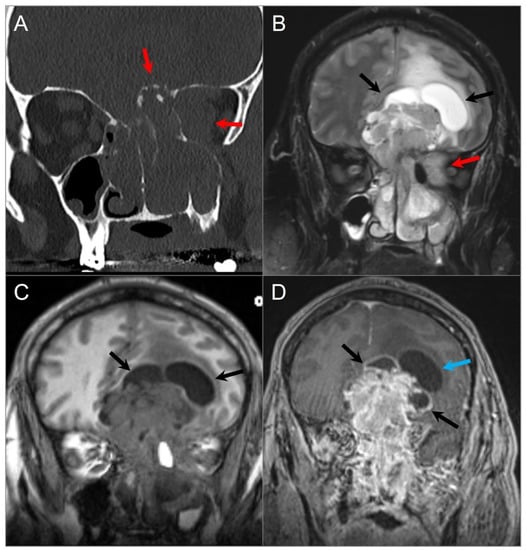

4.2.3. Olfactory Neuroblastoma

4.3. Central Skull Base Tumors

4.3.4. Cholesterol Granuloma